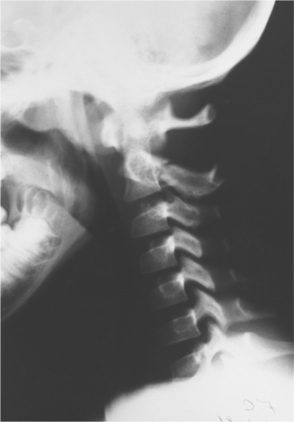

The mechanism of injury influences the type and degree of the spinal cord lesion. Fig. 34-2 shows the flexion damage that is referred to as the hangman’s fracture, related to excessive flexion. Approximately 50% of injuries come from excessive flexion of the spinal column that results in a severe neurologic disorder.18 Fig. 34-3 shows how extension can cause SCI in the elderly population. Fig. 34-4 shows vascular changes that may result from displacement of spinal components. The spinal cord is often violently displaced or compressed momentarily during an injury with forceful flexion, extension, and rotation of the spine. The vertebral body can burst and cause pressure or scatter bone fragments into the spinal cord. Fig. 34-5 illustrates this phenomenon. Complete spinal cord lesions occur in about one third of flexion injuries. With crush fractures of the vertebrae, there is a 75% chance of a complete spinal cord lesion.

Figure 34-2 Fracture of C2 (hangman’s fracture). (From Green NB, Swiontkowski MF, eds: Skeletal trauma in children, ed 3, Philadelphia, 2003, Saunders.)